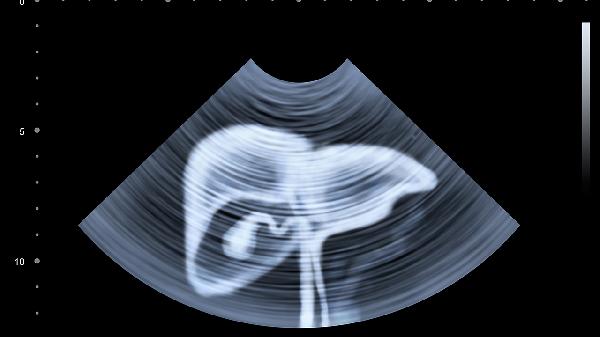

当人体胆囊处于健康状态时,B超声具有光滑均匀的特点。如果发现胆囊壁粗糙,并伴有加厚现象,通常表明胆囊病变,如胆囊炎。胆囊壁厚2.5mm比较正常,如果超过2.5mm说明胆囊可能有炎症,需要第一时间去医院检查治疗。胆囊壁厚5mm表明胆囊存在一定问题,但是否严重仍需进一步检查确认。胆囊壁厚5mm的原因很多,不同原因的严重程度也不同。